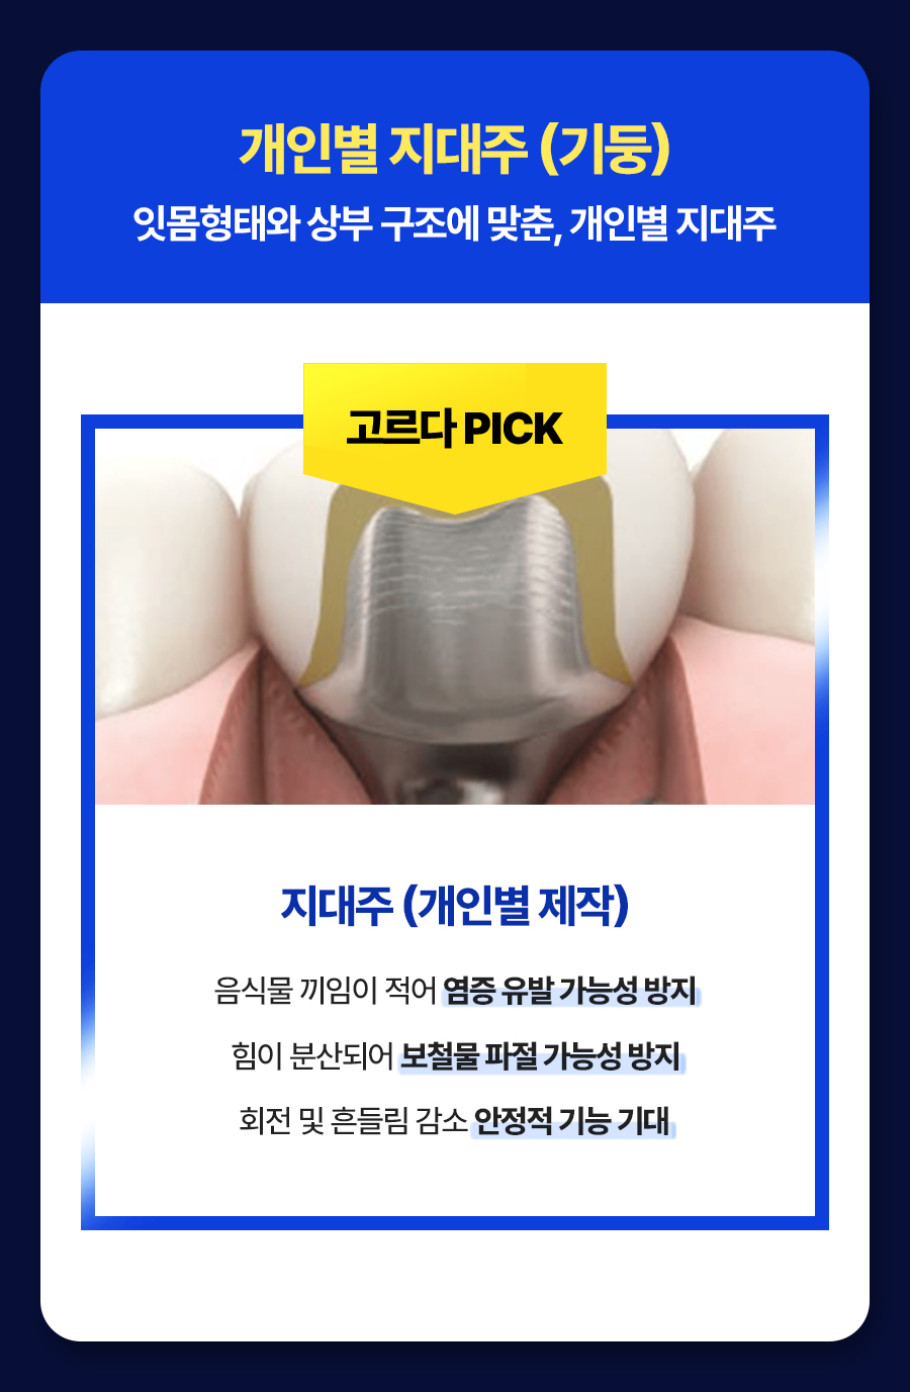

When undergoing full implant treatment, the condition of your oral cavity is the most significant factor. The density and height of the remaining jawbone affect the placement, angle, number, and structure of the implants. Generally, at least 12 implants are placed in both the upper and lower jaws. However, depending on the oral structure, the design may involve only 8 or 10 implants. Of course, reducing the number of implants doesn't necessarily lower the cost. In some cases, expensive materials are used to enhance stability. Therefore, a design tailored to each individual's condition is crucial.

The price typically starts at around 10 million won and can exceed 20 million won. This is based on the structure of a full set of dentures, and the cost can vary by more than 5 million won depending on the individual's gum condition, desired materials, and denture type. This is why dental clinics provide various options before starting treatment. The terminology and methods may seem difficult at first, but understanding them will clarify which option is best for you. The cost of Seomyeon implants can be flexibly adjusted depending on the chosen configuration.

To find the right configuration and treatment plan for you, it's necessary to listen to detailed explanations and carefully compare the required conditions. The cost of Seomyeon implants is not simply determined by a single number. It's a process of carefully adjusting the structure, materials, and condition, requiring extra caution. Even if it seems overwhelming at first, you can find a solution by gradually organizing your thoughts. A small choice can affect the overall treatment outcome, so a careful approach is needed.